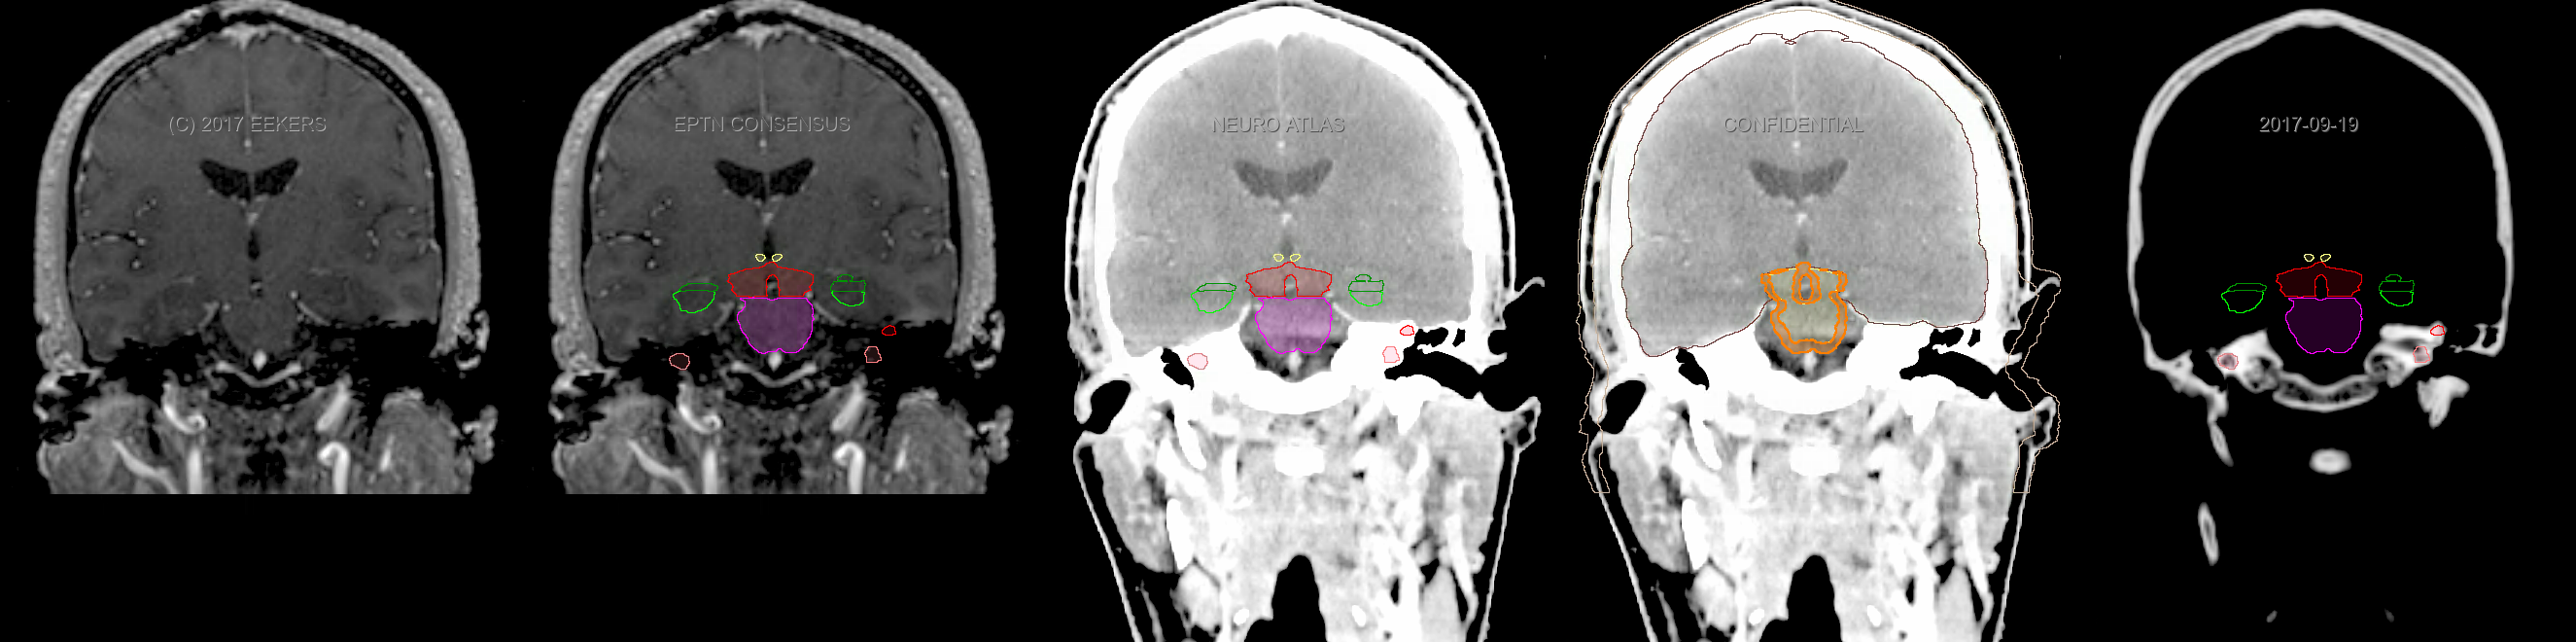

Three-dimensional delineation of the fifteen consensus OARs for neuro-oncology are shown on CT and 3 Tesla (3T) MR images (slice thickness 1 mm with intravenous contrast agent). All are presented in transversal, sagittal and coronal view.

From left to right: MR without structures, MR with structures, CT (WW/WL 120/40) with structures, CT (WW/WL 120/40) with Brain and Brainstem Surface, CT (WW/WL 1500/120)with structures